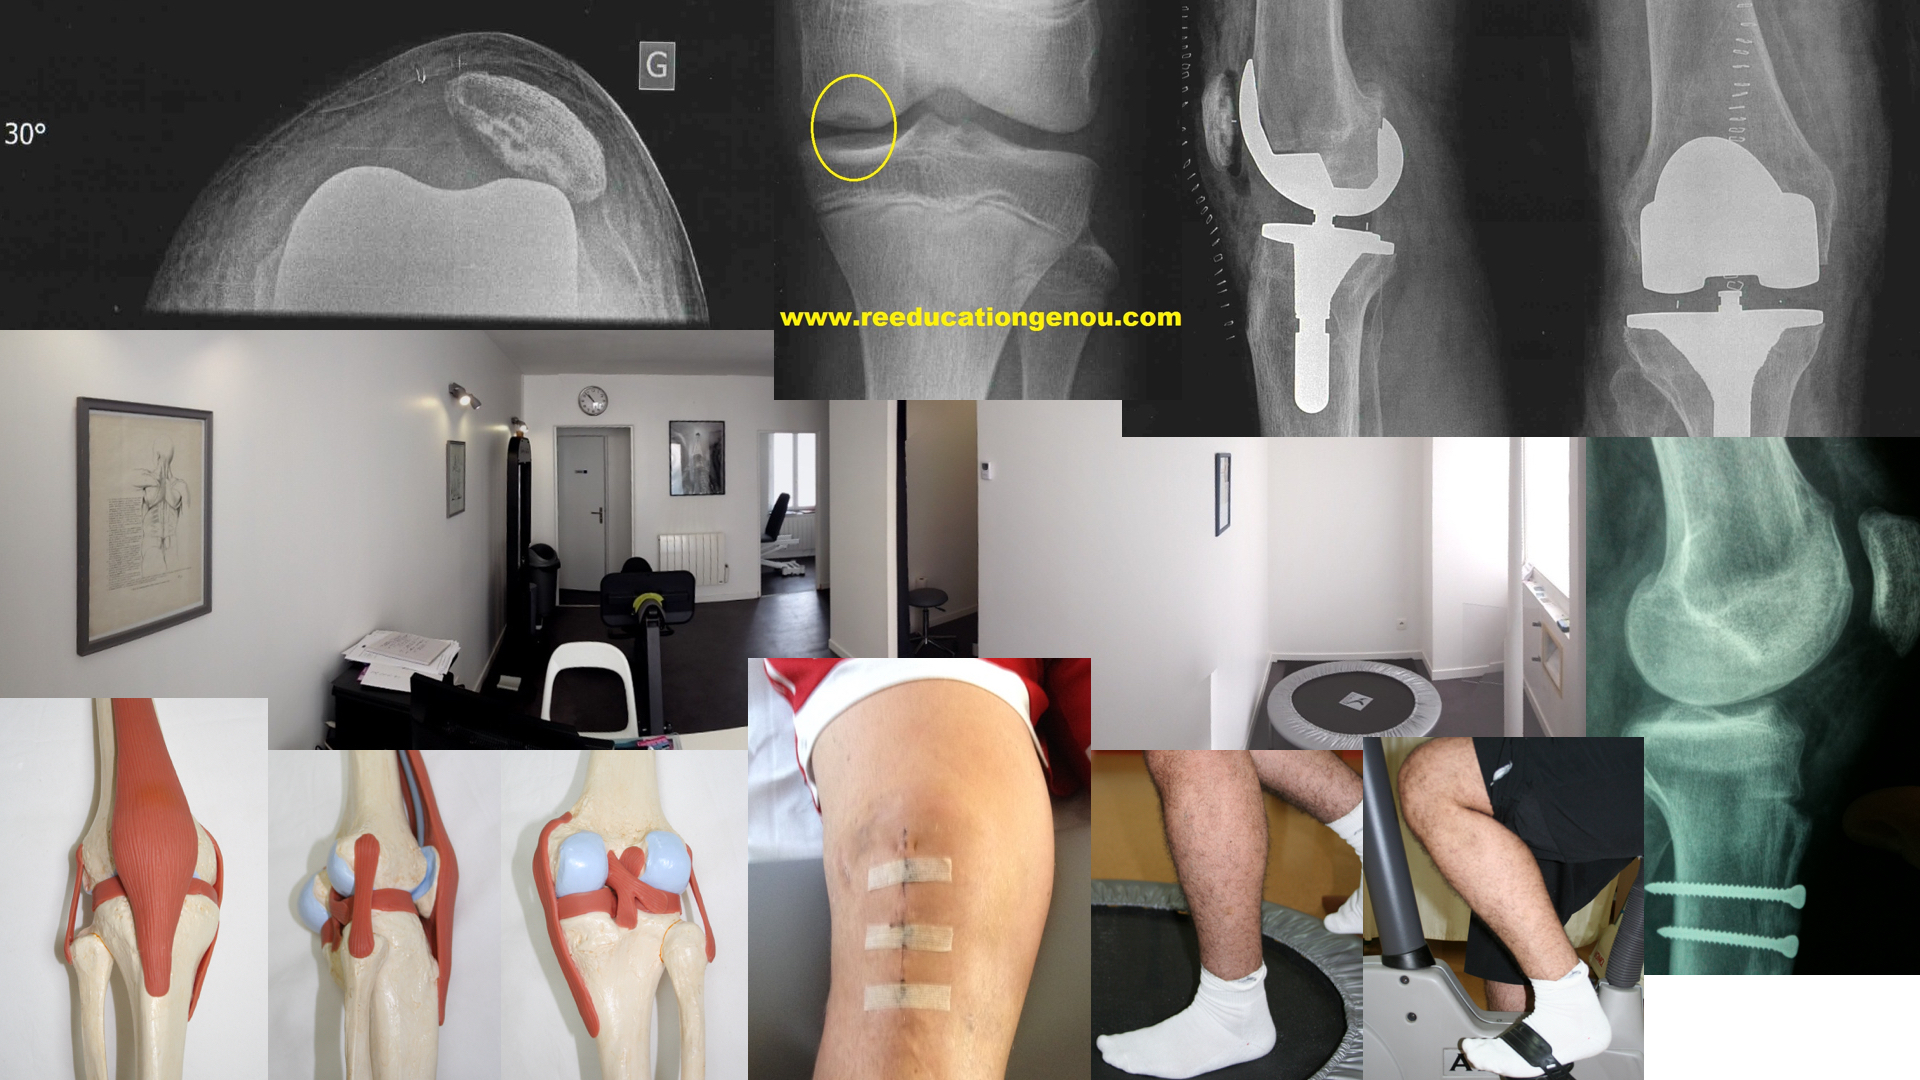

Du 15è au 21è jours post-opératoire à 2 mois environ

toutes les ligamentoplasties sont en rééducation les KJ comme les Didt !

DiDt sur presse, travail à 2 jambes (photo de 2006, cabinet des Maussins, 75019)